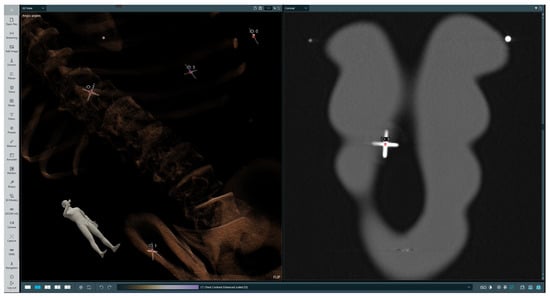

2.1. Proposed Solution

2.2. Clinical Workflow